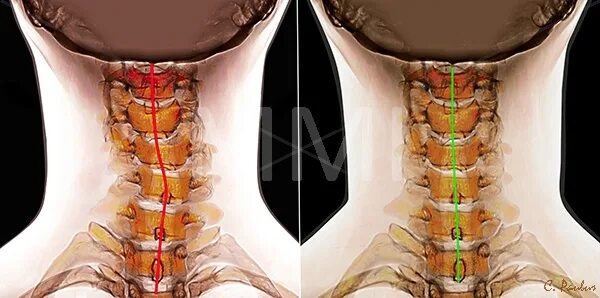

Как исправить шейный отдел